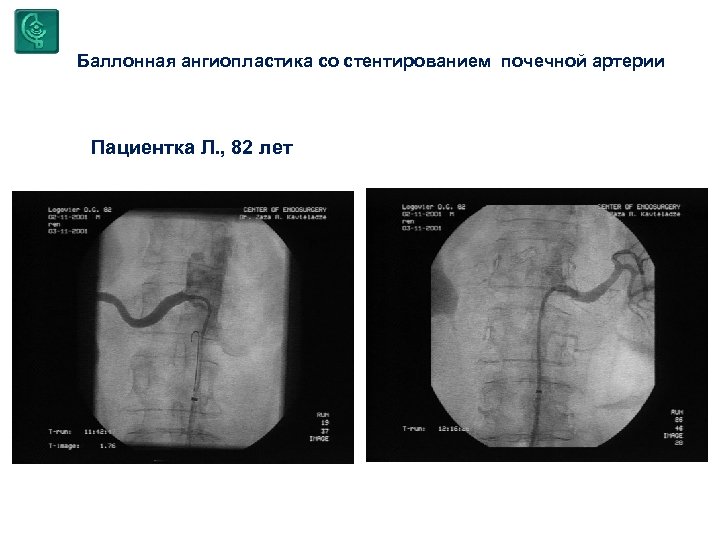

Баллонная ангиопластика со стентированием почечной артерии Пациентка Л. , 82 лет

Баллонная ангиопластика со стентированием почечной артерии Пациентка Л. , 82 лет

Баллонная ангиопластика со стентированием почечной артерии Пациентка Л. , 82 лет

Баллонная ангиопластика со стентированием почечной артерии Пациентка Л. , 82 лет